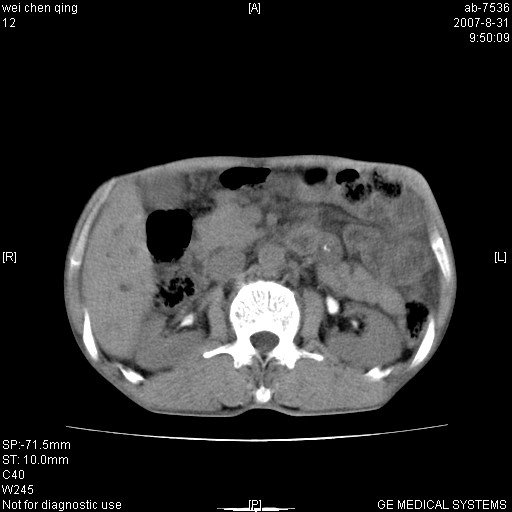

以下是引用zjzjr在2007-8-31 14:38:00的发言:[br]胰头癌伴肝内胆管扩张可能性大。

以下是引用zyyzzy在2007-8-31 14:34:00的发言:[br]该病人肝内胆管扩张,胆囊及胆总管未见明显扩张。在倒数第9层图像上可看到左右肝管结合部(肝总管)有软组织影,此处应薄层扫描。考虑肝总管占位(ca)、腹水。[br]